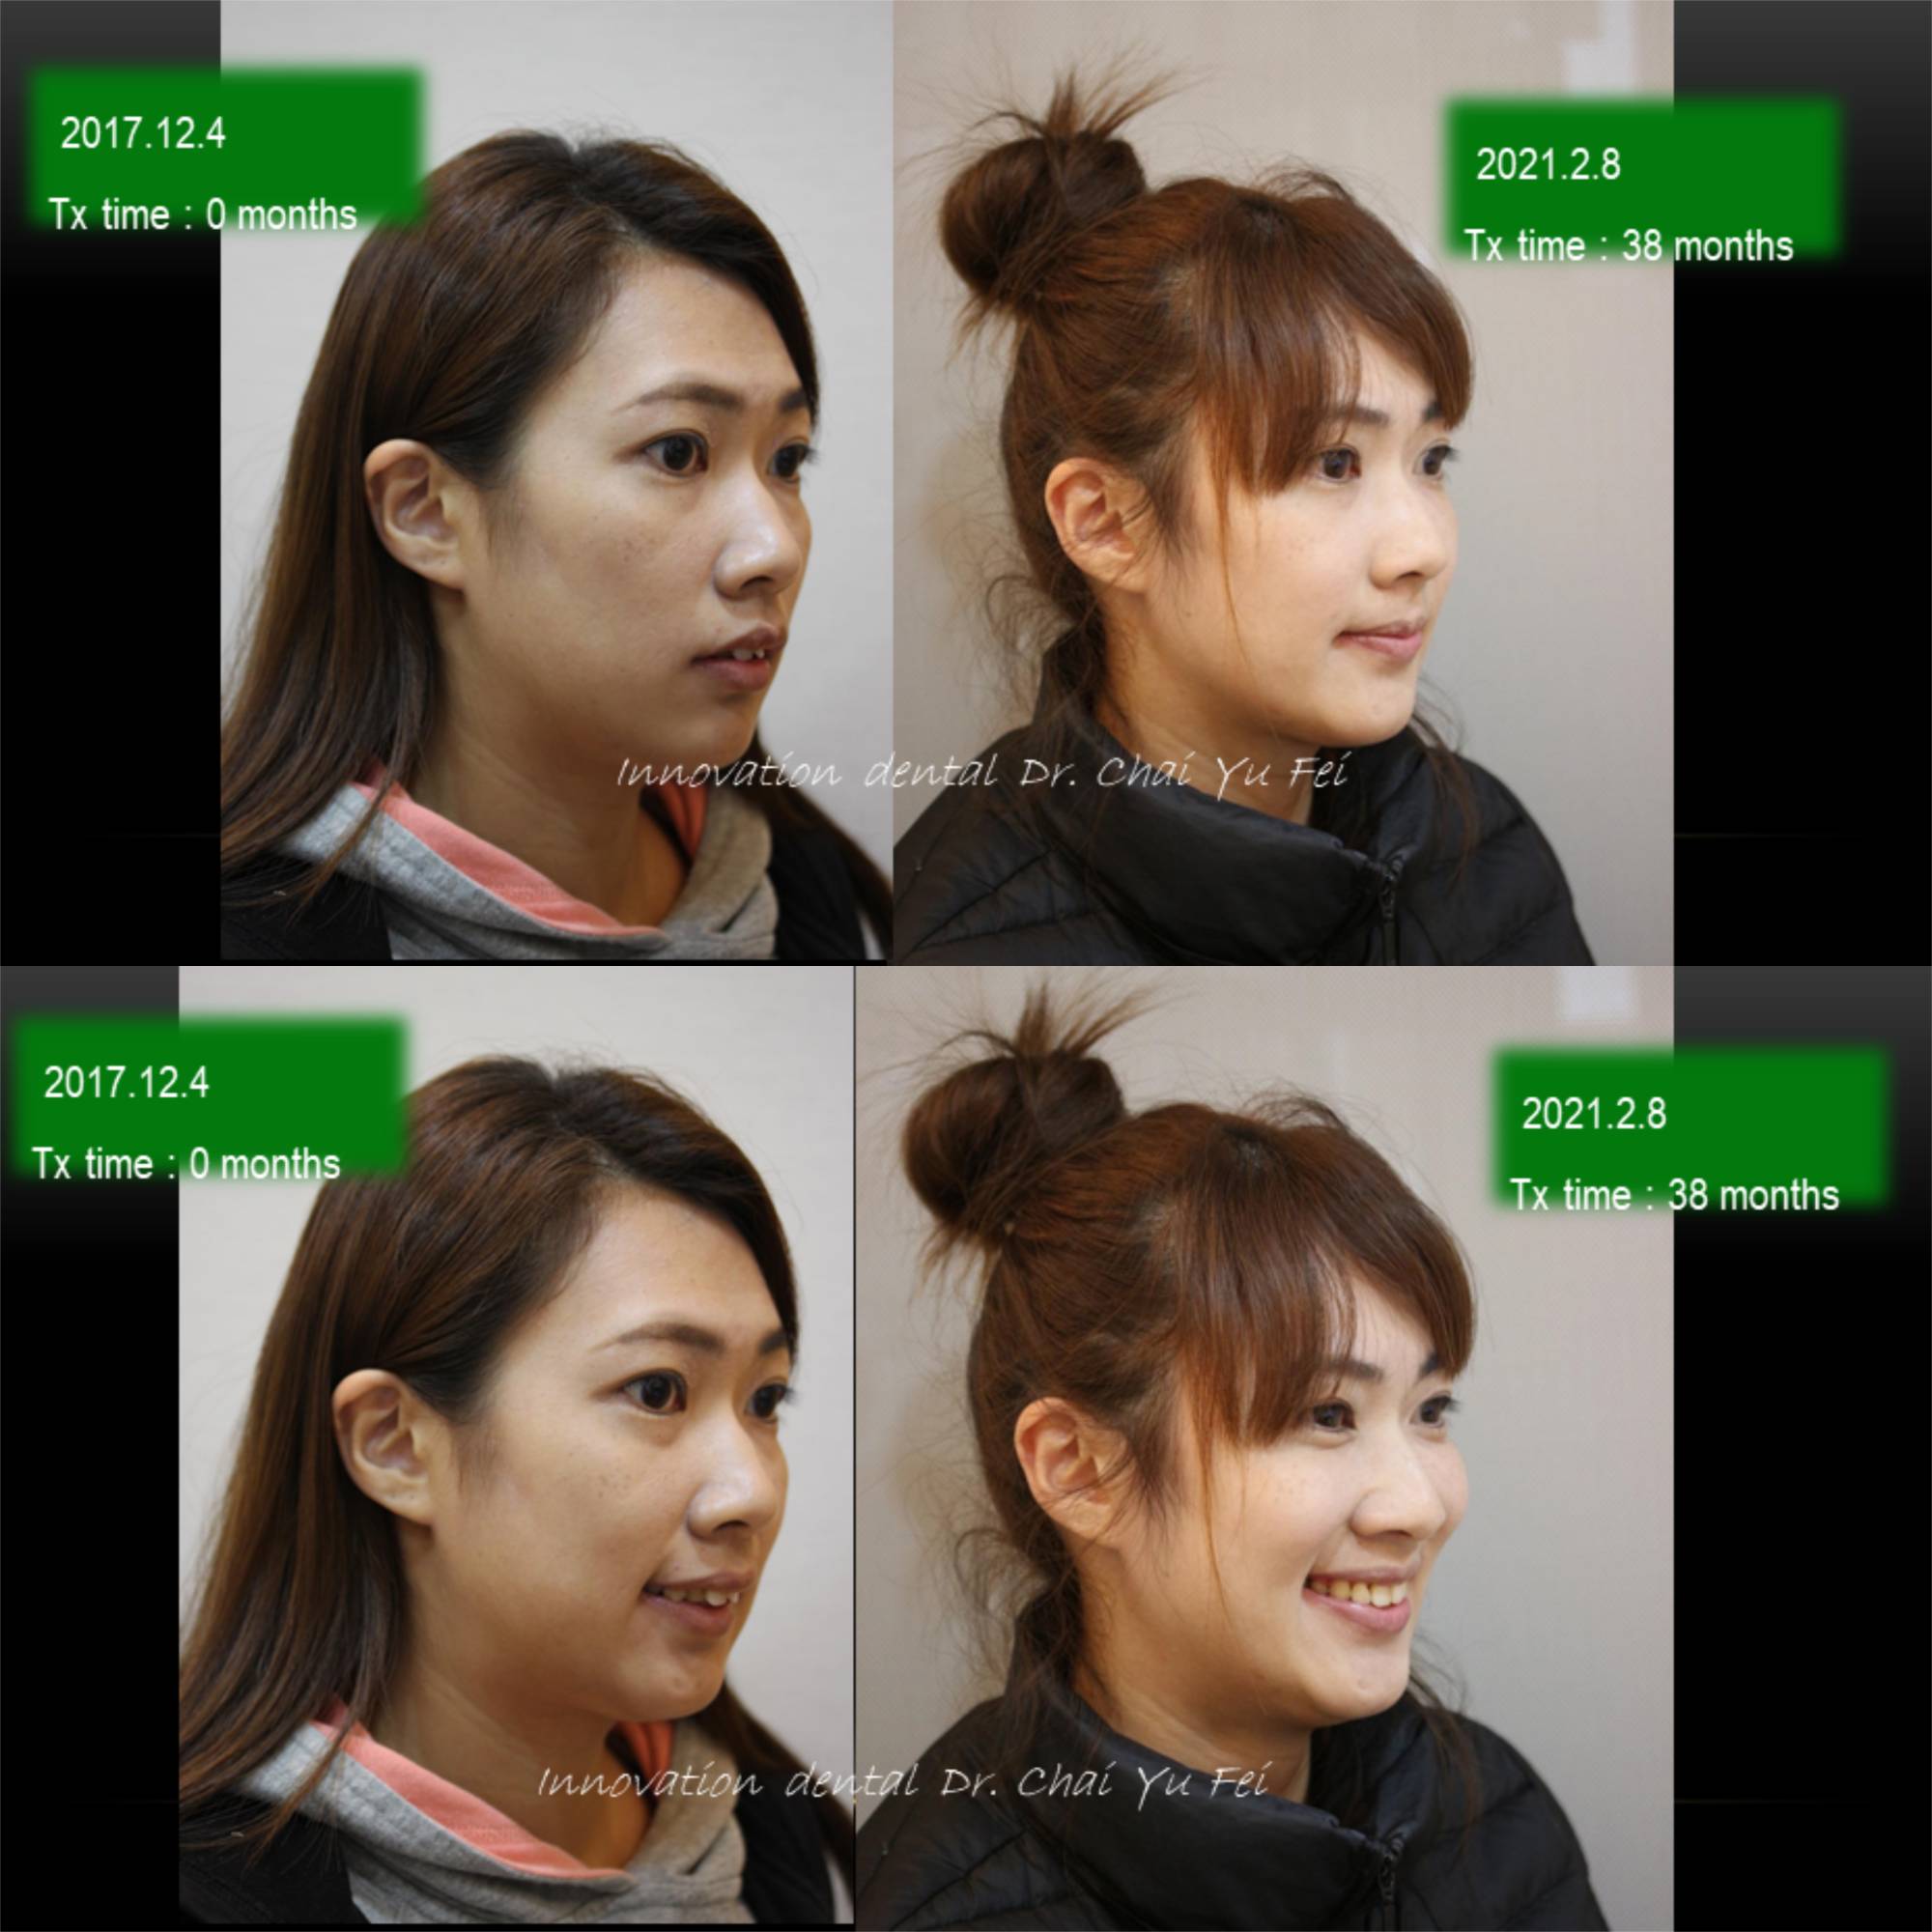

以這次黃小姐的案例來說,可以從照片中看到,由於上顎齒列狹窄,前牙角度往外傾斜,進而造成唇形前突不理想。

為了避免過度治療而傷害了原本可以恢復青春美麗的外觀,翟醫師決定採取上顎拔2顆小臼齒,下顎不要拔牙,在保留最多自然牙的情況下,改善下顎角度達到最美麗的外觀輪廓跟理想的咬合。

拔牙矯正前後變化,改善嘴型前突

看到這樣的治療結果,相信您應該對拔牙沒有那麼擔心了,不論是拔4顆或是拔2顆牙齒,我們無非都是為了讓出更多空間,來把齒列調整整齊,選擇拔牙的牙位通常也是重複性高的小臼齒,或是有病灶的牙齒,具有重要功能及不可取代性的牙齒我們不會隨便拔除,即使要犧牲牙齒,我們設計的治療計畫也會將犧牲降到最小,而且完全不影響功能以及外觀。治療完成後,一樣有好的微笑曲線跟理想穩定的咬合。